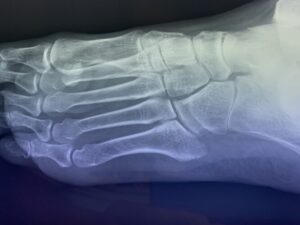

第5中足骨基底部骨折でお悩みの方へ(下駄骨折)の総合ガイド|当院が実践す…